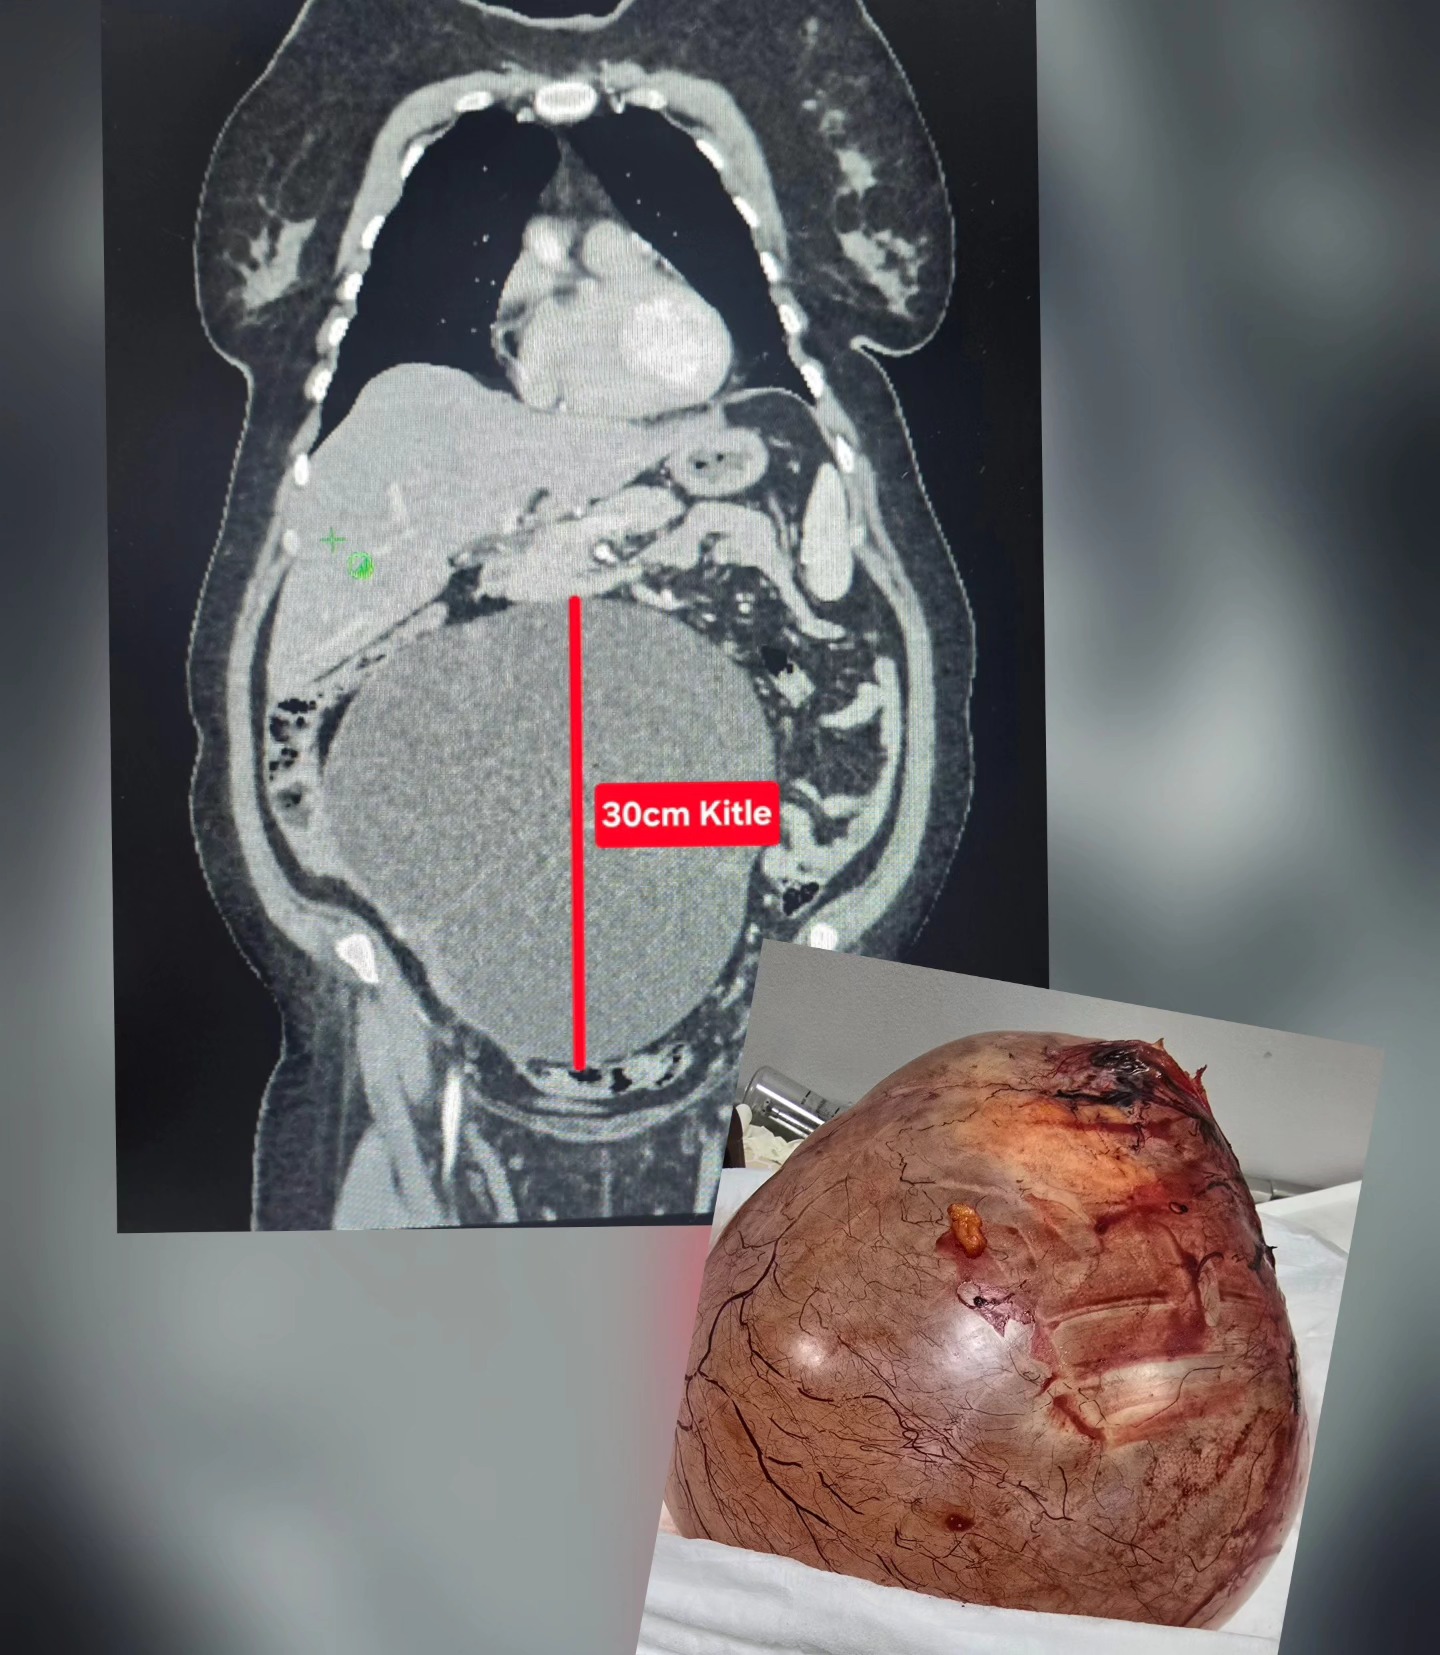

Uşak’ta şiddetli ağrı, kabızlık ve şişlik şikayeti bulunan bir vatandaş, Uşak Özel Öztan Hastanesi’ne başvurdu ve burada yapılan kontrollerde karın bölgesinde büyüyen ve 30 santimetreye ulaşan dev bir kitle tespit edildi. Özel Öztan Hastanesi’ndeki Kadın Hastalıkları ve Doğum ve Genel Cerrahi ekibi, tarafından yapılan bir operasyonla dev kitle çıkarıldı ve hasta yeniden sağlığına kavuştu. Genel Cerrah Op. Dr. Aydın Tükenmez, yapılan operasyonun detayları hakkında bilgiler verdi.

Yaklaşık 3 saat süren ameliyatta kitle eksizyonu, apendektomi, omentektomi ve TAH-BSO olarak adlandırılan operasyon uygulandı. Uşak Özel Öztan Hastanesi Yönetimi, operasyonda görev alan ve özveriyle çalışan tüm sağlık personeline teşekkür ederken, bu tür şikayetleri olan vatandaşların en yakın sağlık kurumuna başvurarak kapsamlı bir tahlil ve tetkik yaptırması ve ilgili uzmanlardan destek alması istendi.